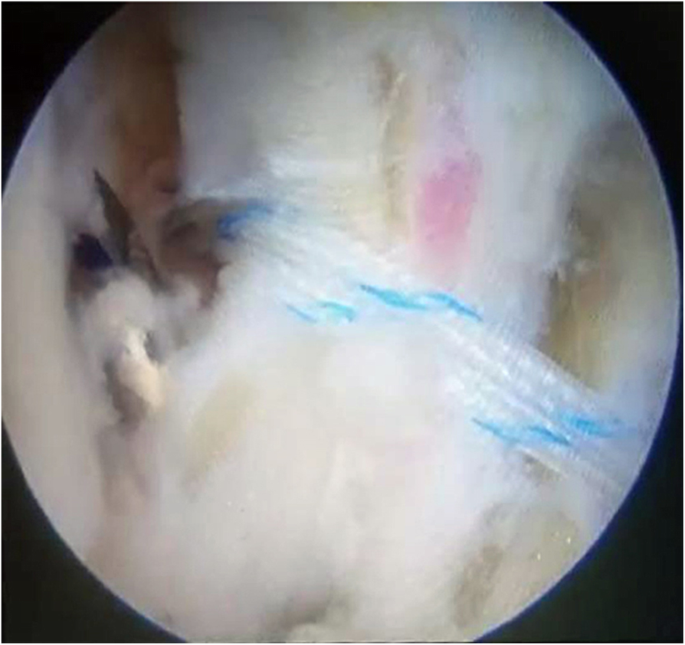

The arthroscopic-assisted Brostrom technique was performed following the same procedure described in a previous study [24]. To repair the ATFL, two initial anterior arthroscopic portals were utilized. The anterior lateral ankle joint was completely debrided to avoid potential postoperative impingement as far as possible, and the anterior distal face of the fibula was debrided subsequently with a shaver to create raw bone for promoting the adherence of soft tissues. Then, an accessory anterolateral (acAL) portal was created at the site 1.5 cm anterior to the tip of the fibula, passing through just proximal to the site of the raw bone prepared previously (Fig. 3). A drill/anchor guide was placed through the acAL portal and positioned in the raw bone prepared in the fibula, which was drilled for the purpose of inserting one or two suture anchors (2.8-mm, Arthrex, USA) inside (Fig. 4). Then, a tissue-penetrating instrument was used to penetrate the ATFL remnant (Fig. 5). Thereafter, the sutures were grasped to pass through the ATFL and then pulled cautiously to tighten the ATFL.